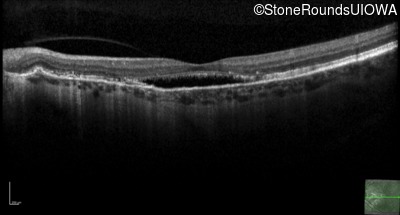

Age at visit: 60 years